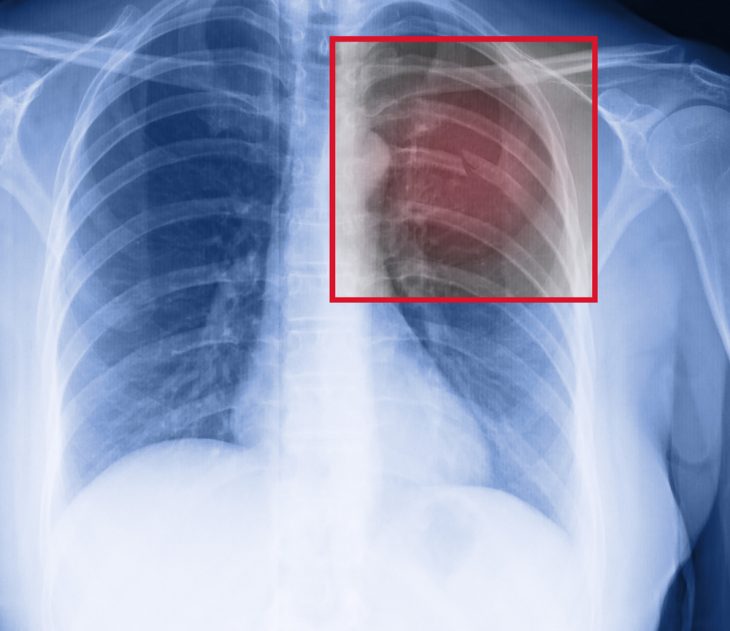

Для уточнения степени повреждения ребер и выявления скопления крови и других поражений могут назначаться такие дополнительные методы обследования:

- рентгеновские снимки (в переднезадней проекции);

- КТ;

- УЗИ грудной клетки.

Переломы ребер могут быть односторонними и двухсторонними, единичными и множественными, со смещением и без оного, открытыми и закрытыми. Опасность представляют травмы, которые сопровождаются повреждением внутренних органов и нарушением дыхания. Но, диагностировать перелом может только специалист – на основе внешнего осмотра и рентгенографии.